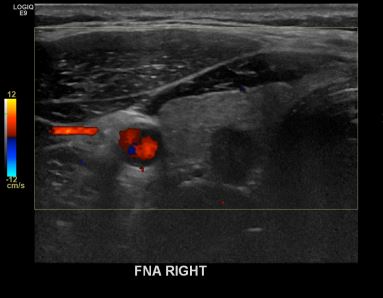

상기환자  외부검사이상소견으로 내원하신 50대 초반 남성분으로 의심스러운 갑상선 우측혹 세포검사진행후 갑상선암으로 진단되었습니다